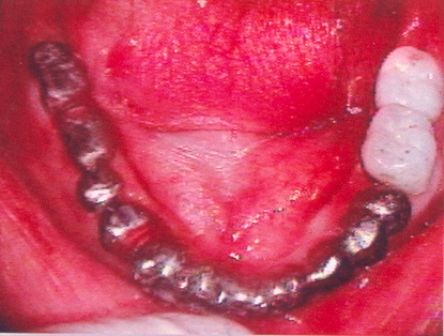

Subperiosteal implantlar - bunlar, dişeti dokusunun hemen altındaki çene kemiğine takılan metal bir çerçeveden oluşurlar. Dişeti iyileştiğinde, çerçeve çene kemiğine sabit hale gelir. Çerçeveye takılan materyaller, dişetlerinden dışarı çıkar. Endosteal implantlarda olduğu gibi, yapay dişler, daha sonra implantalara monte edilir.